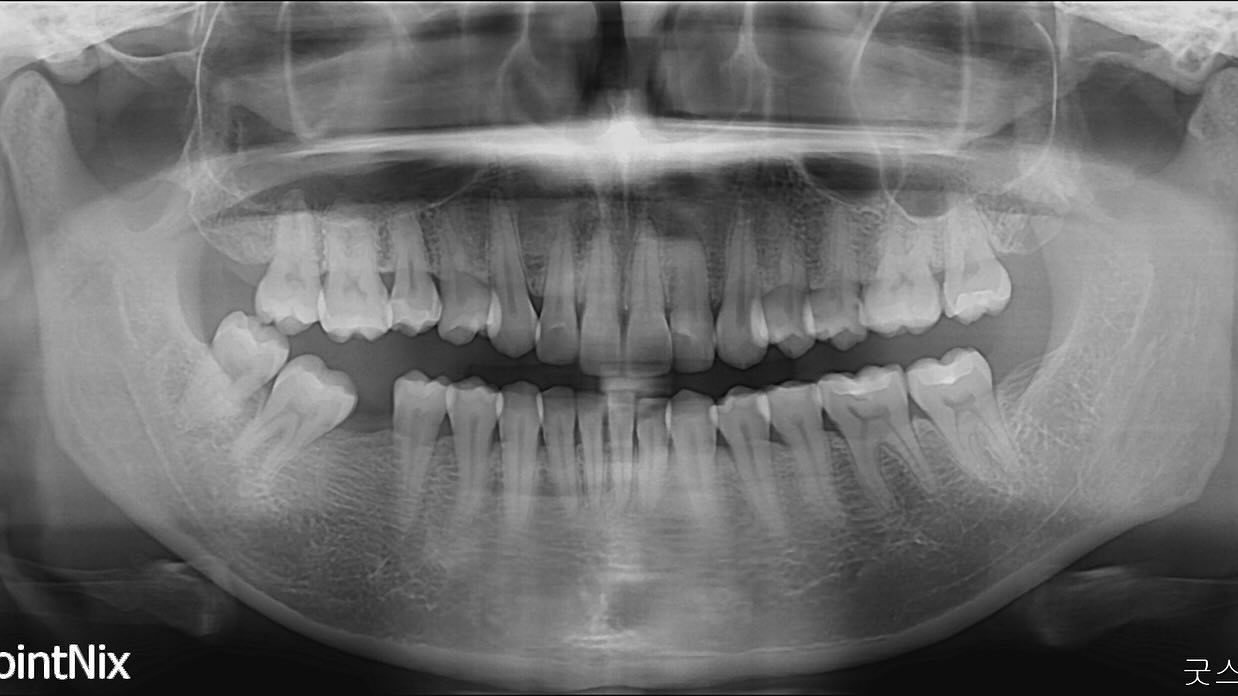

molar protraction

non ext

lip protrusion